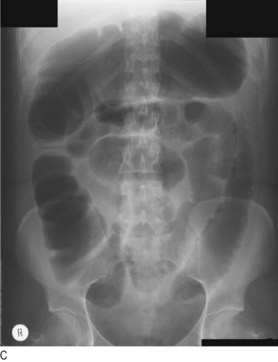

Fig. 8.29 Radiography in gastrointestinal disease.

(A) Air under the diaphragm on chest X-ray due to perforated duodenal ulcer. (B) Dilated small bowel due to acute intestinal obstruction. (C) Dilated large bowel due to toxic megacolon. (D) Dilated loop of large bowel due to sigmoid volvulus.